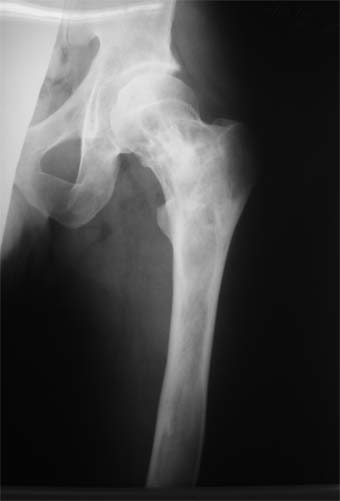

Коллеги!Пациент Д., 35 лет, В 1985 году был поставлен диагноз гемигипоплазия правой нижней конечности. Укорочение 5 см, в 1987 году остеотомия правого бедра, аппарат 4 месяца, удлинили на 2 см из-за нагноения спиц аппарат сняли. В настоящее время Жалобы на дискомфорт, тяжесть в левом бедре, голени при длительной ходьбе, при длительном лежании на левом бедре. Эти жалобы беспокоят втечение 5-6 лет. В 1999 году выявили "изменения" (со слов больного, выписки нет на руках) бедренной кости и костей голени слева. Тогда же предложили в ЦИТО срочно делать какую-то операцию. При осмотре: Правая нижняя конечность. Имеются рубцы на правом бедре по наружной и внутренней поверхностям. Ограничения движений в коленном суставе нет. Кровоснабжение, иннервация сохранены. Левая нижняя конечность. Левое бедро увеличено в объеме, при пальпации пальпируется бедренная кость большего диаметра по сравнению с левым бедром. Пальпация безболезненна. Голень обычной формы. Объем движений в суставах полный. Кровоснабжение, иннервация сохранены. Имеется разница в длине конечностей правая короче на 4-5 см за счет бедра и голени. В приложении вид больного и рентгенограммы бедра 2001 год и 2005 год. Что бы это могло быть? О чем можно думать? Онкология? С уважением Коробушкин Глеб Владимирович Российский государственный медицинский университет кафедра травматологии, ортопедии и ВПХ, доцент

В настоящее время имеется умеренный рубцовый процесс правого бедра не мешающий на объем движений в суставах. В коленном суставе слева бедро обычное, голень - булавовидное утолщение проксимального конца большеберцовой кости. На рентгенограммах тотальное поражение кости с увлечением в процесс проксимального эпиметафиза, поражение характерно для болезни Campanatsehi

У больного полиоссальноая форма фиброзной дисплазии с поражение левой бедренной и большеберцовой кости. На рентгенограммах - тотальное разрастание и остончение кортикального слоя. Имеется удлинение левой нижней конечности на 2,5-3 см за счет голени. Больному показано оперативное лечение левой большеберцовой кости.